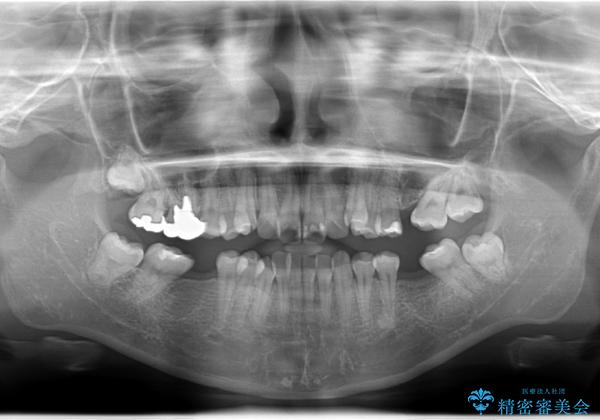

- 患者様は、下顎両側の第1大臼歯(6番)と右上6番の欠損を主訴に来院されました。

通常であればインプラントによる補綴が第一選択となる症例でしたが、患者様ご自身がインプラントを希望されなかったため、矯正治療によって欠損部の閉鎖を図る方針としました。

同時に、親知らず(智歯)の萌出や位置も考慮し、咬合全体のバランスを改善する矯正治療計画を立案しました。

ワイヤー矯正を用いて、欠損部の閉鎖を目的とした後方からの歯の挺出・移動を行いました。

特に、親知らずを活用し、奥歯の噛み合わせを構築することに重点を置きました。

最終的には予定通りインプラントを使用せずに欠損部を閉鎖し、咬合も安定させることができました。